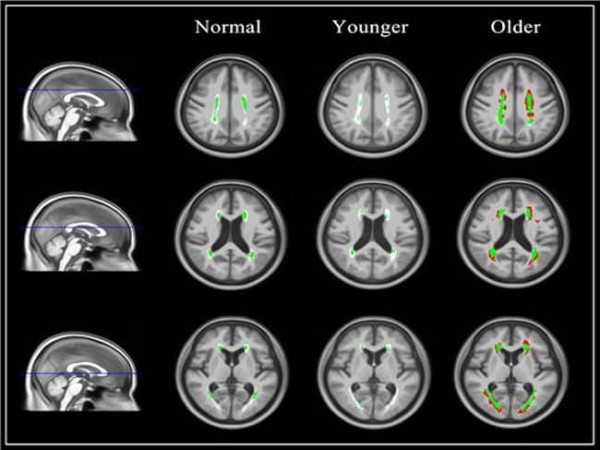

대표적으로 백질고강도신호가 실제 나이와 동일한 케이스, 실제 나이보다 적은 케이스, 실제 나이보다 많은 케이스 총 3명을 선정해 백질고강도 신호를 백질고강도신호 확률지도에 겹쳐 표기했을 때, 백질고강도신호 연령이 실제 나이보다 많은 사람에게서는 확률지도 범위를 넘어서는 신호가 관찰됐다. 세 사람 모두 MRI 촬영 당시에는 인지기능이 정상이었지만 백질고강도신호 연령이 실제 나이보다 많았던 사람만 2년 후 인지장애가 발생해, 백질고강도신호가 실제 연령대에 비해 높으면 인지장애 발생 위험이 높다는 것을 확인할 수 있었다.

그림2. 왼쪽부터 백질고강도신호연령이 실제 나이와 동일한 normal 1명, 나이에 비해 적은 younger 1명, 나이보다 많은 older 1명, 총 3명의 백질고강도신호를 확률지도에 겹쳐서 표기한 그림. 밝은 회색은 정상 노인의 확률지도, 초록색은 확률지도 범위 내의 백질고강도신호, 붉은 부분은 확률지도를 넘는 범위의 신호이다.